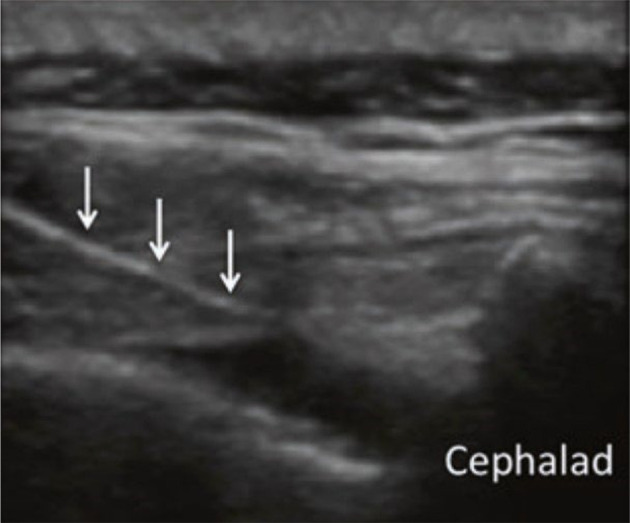

Methods: A randomized double-blinded clinical trial was conducted involving 52 PLSS patients who were randomly assigned to either the CESI group or the S1-TFESI group. The patients were positioned prone. A linear transducer with a curve at a low frequency (2 - 5 MHz) was used to visualize the area. An aseptically prepared puncture site was used to insert a 2- to 5-MHz curved ultrasound probe with an ultrasound gel to identify the articular processes of the lower lumbar vertebrae and the posterior sacral surface. The probe was then positioned longitudinally to the para-sacral area, about 2 cm lateral to the midline. The articular process represented the L5/S1 level at the farthest caudal side, and the S1 posterior sacral foramen was represented by the concavity at the posterior sacral surface that was somewhat caudal. The probe was angled caudally to provide enough room for the needle to enter the S1 foramen. The injection site for the needle tip was the S1 foramen. A combination of triamcinolone (40 mg, 1 mL), normal saline (2 mL), and ropivacaine (0.2%) was administered. For TFS1 ESI, 5 mL of the combination was used. For CESI, the sacral hiatus was palpated in the prone position, and a linear high-frequency transducer was placed transversely to obtain a transverse view of the sacral hiatus. A combination of triamcinolone 40 mg and ropivacaine (0.2%) totaling 10 mL was employed. The Numerical Rating Scale (NRS) and Oswestry Disability Index (ODI) were used to assess patients' preoperative and postoperative conditions, and adverse events were recorded. Follow-up was conducted one week and one month after the procedures.